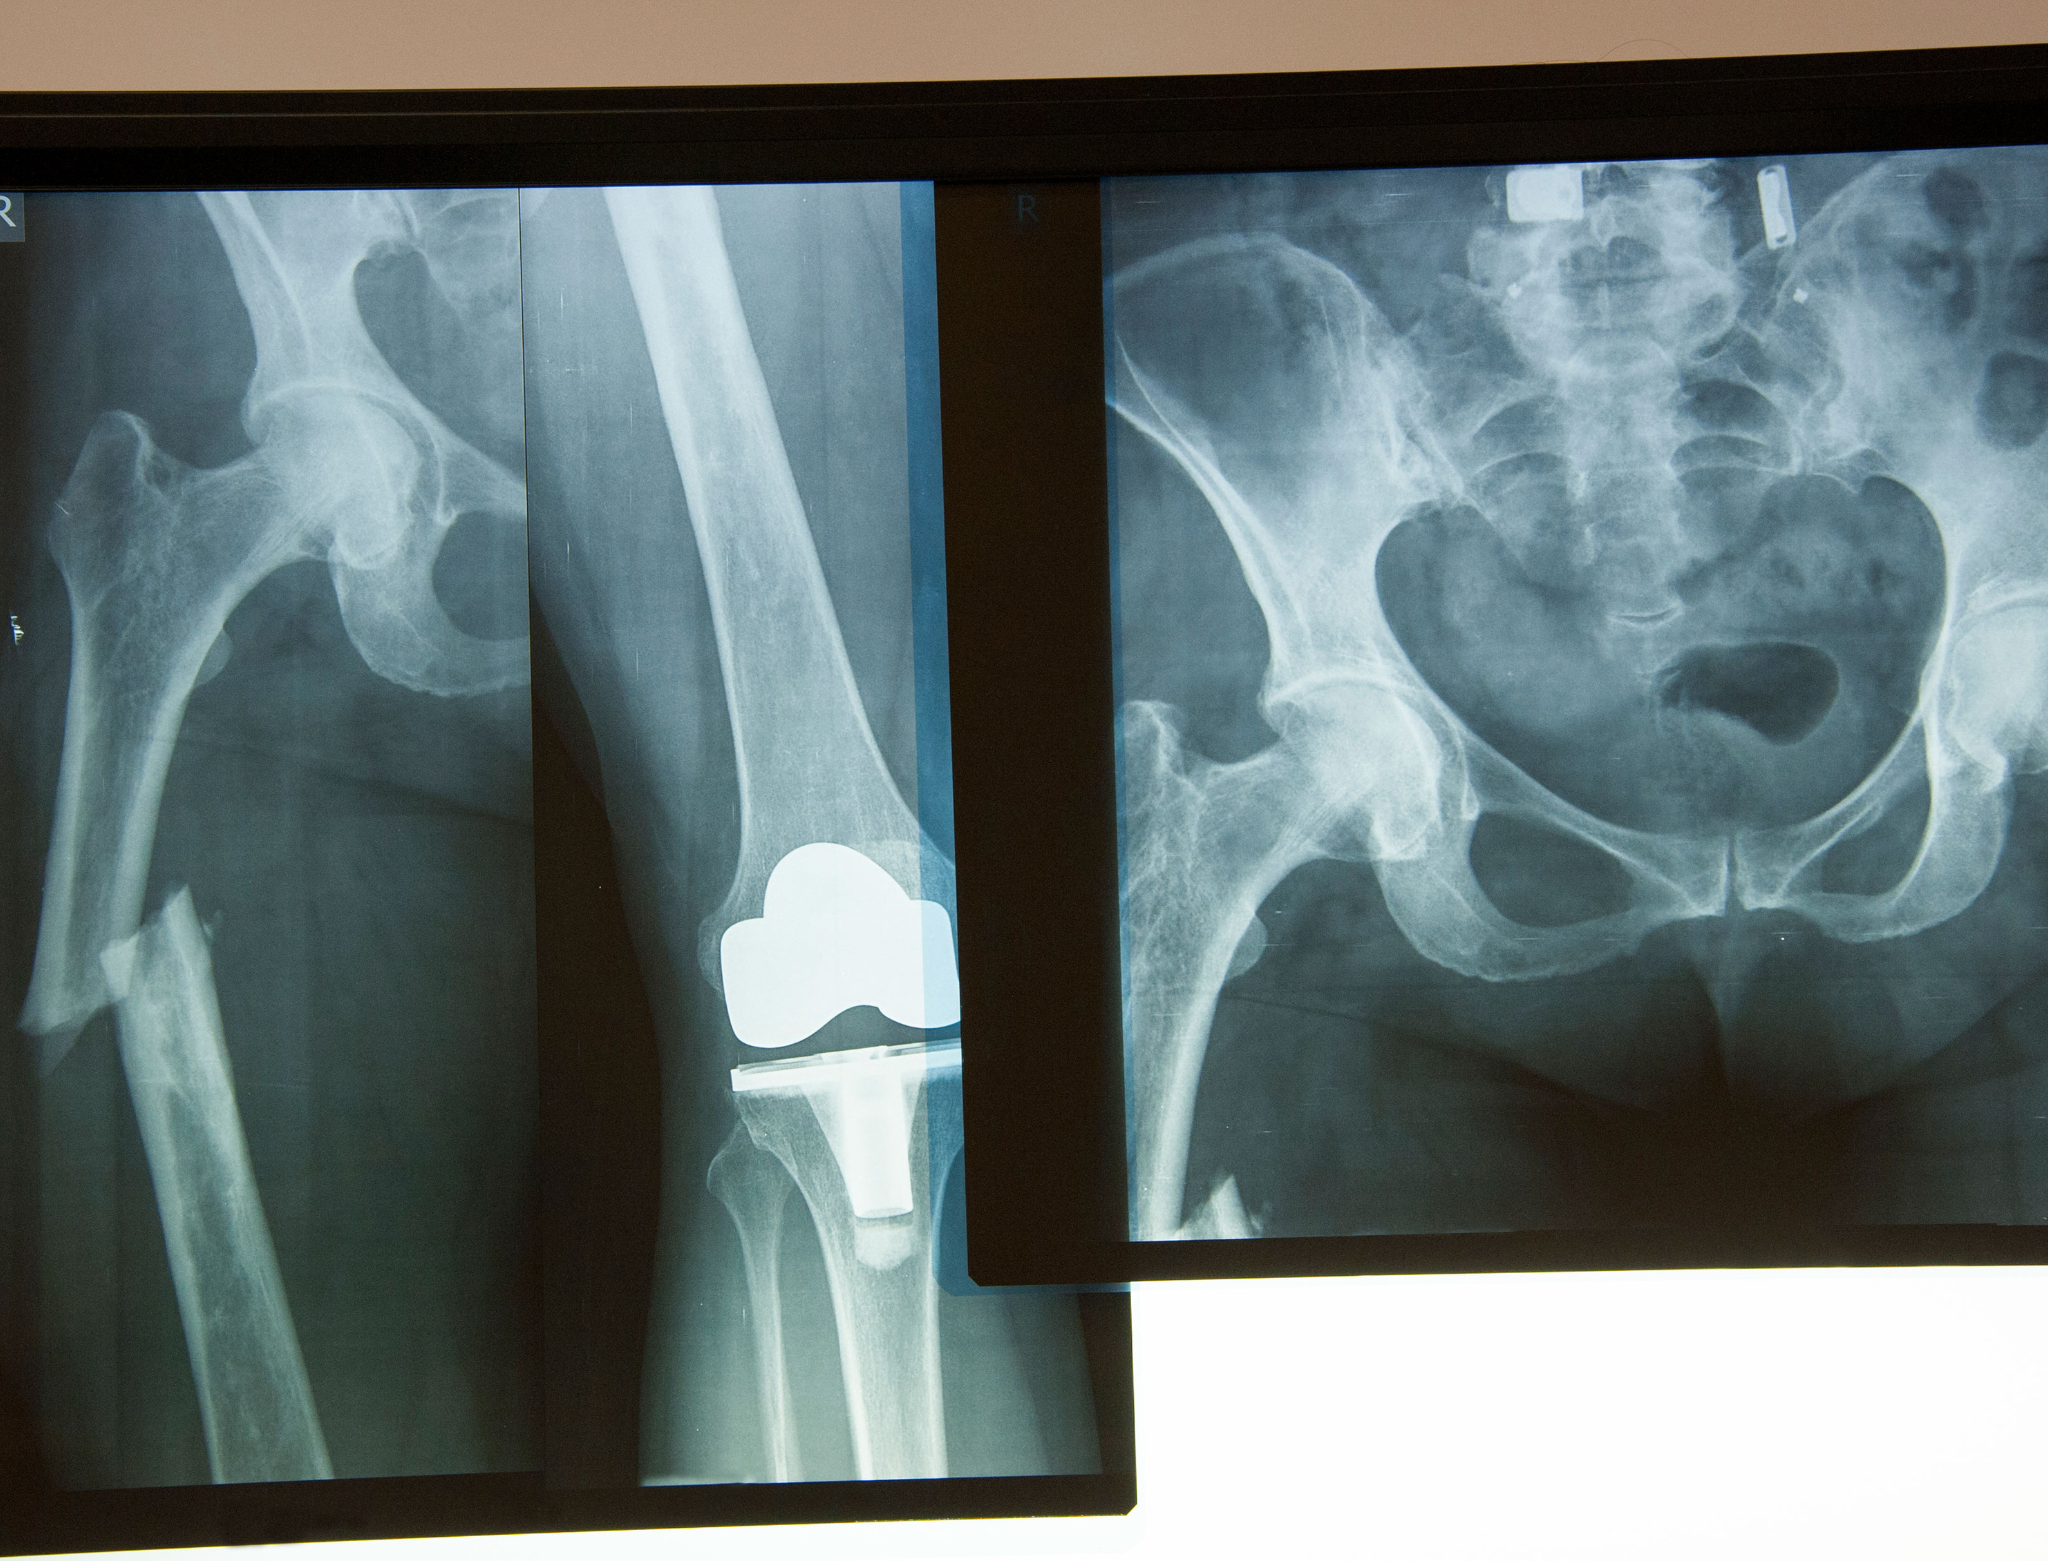

Hip Fracture Surgery

What is a Hip Fracture?

Various types of accidents and their causes injury to your upper part of the thighbone (femur) leading to a hip fracture. Hip fractures can also be common among the elders due to natural and inevitable weakening of bone structures and due to overall decline in the general health. Almost all hip fractures cause severe pain and may require surgery instantly except in a few rare cases.